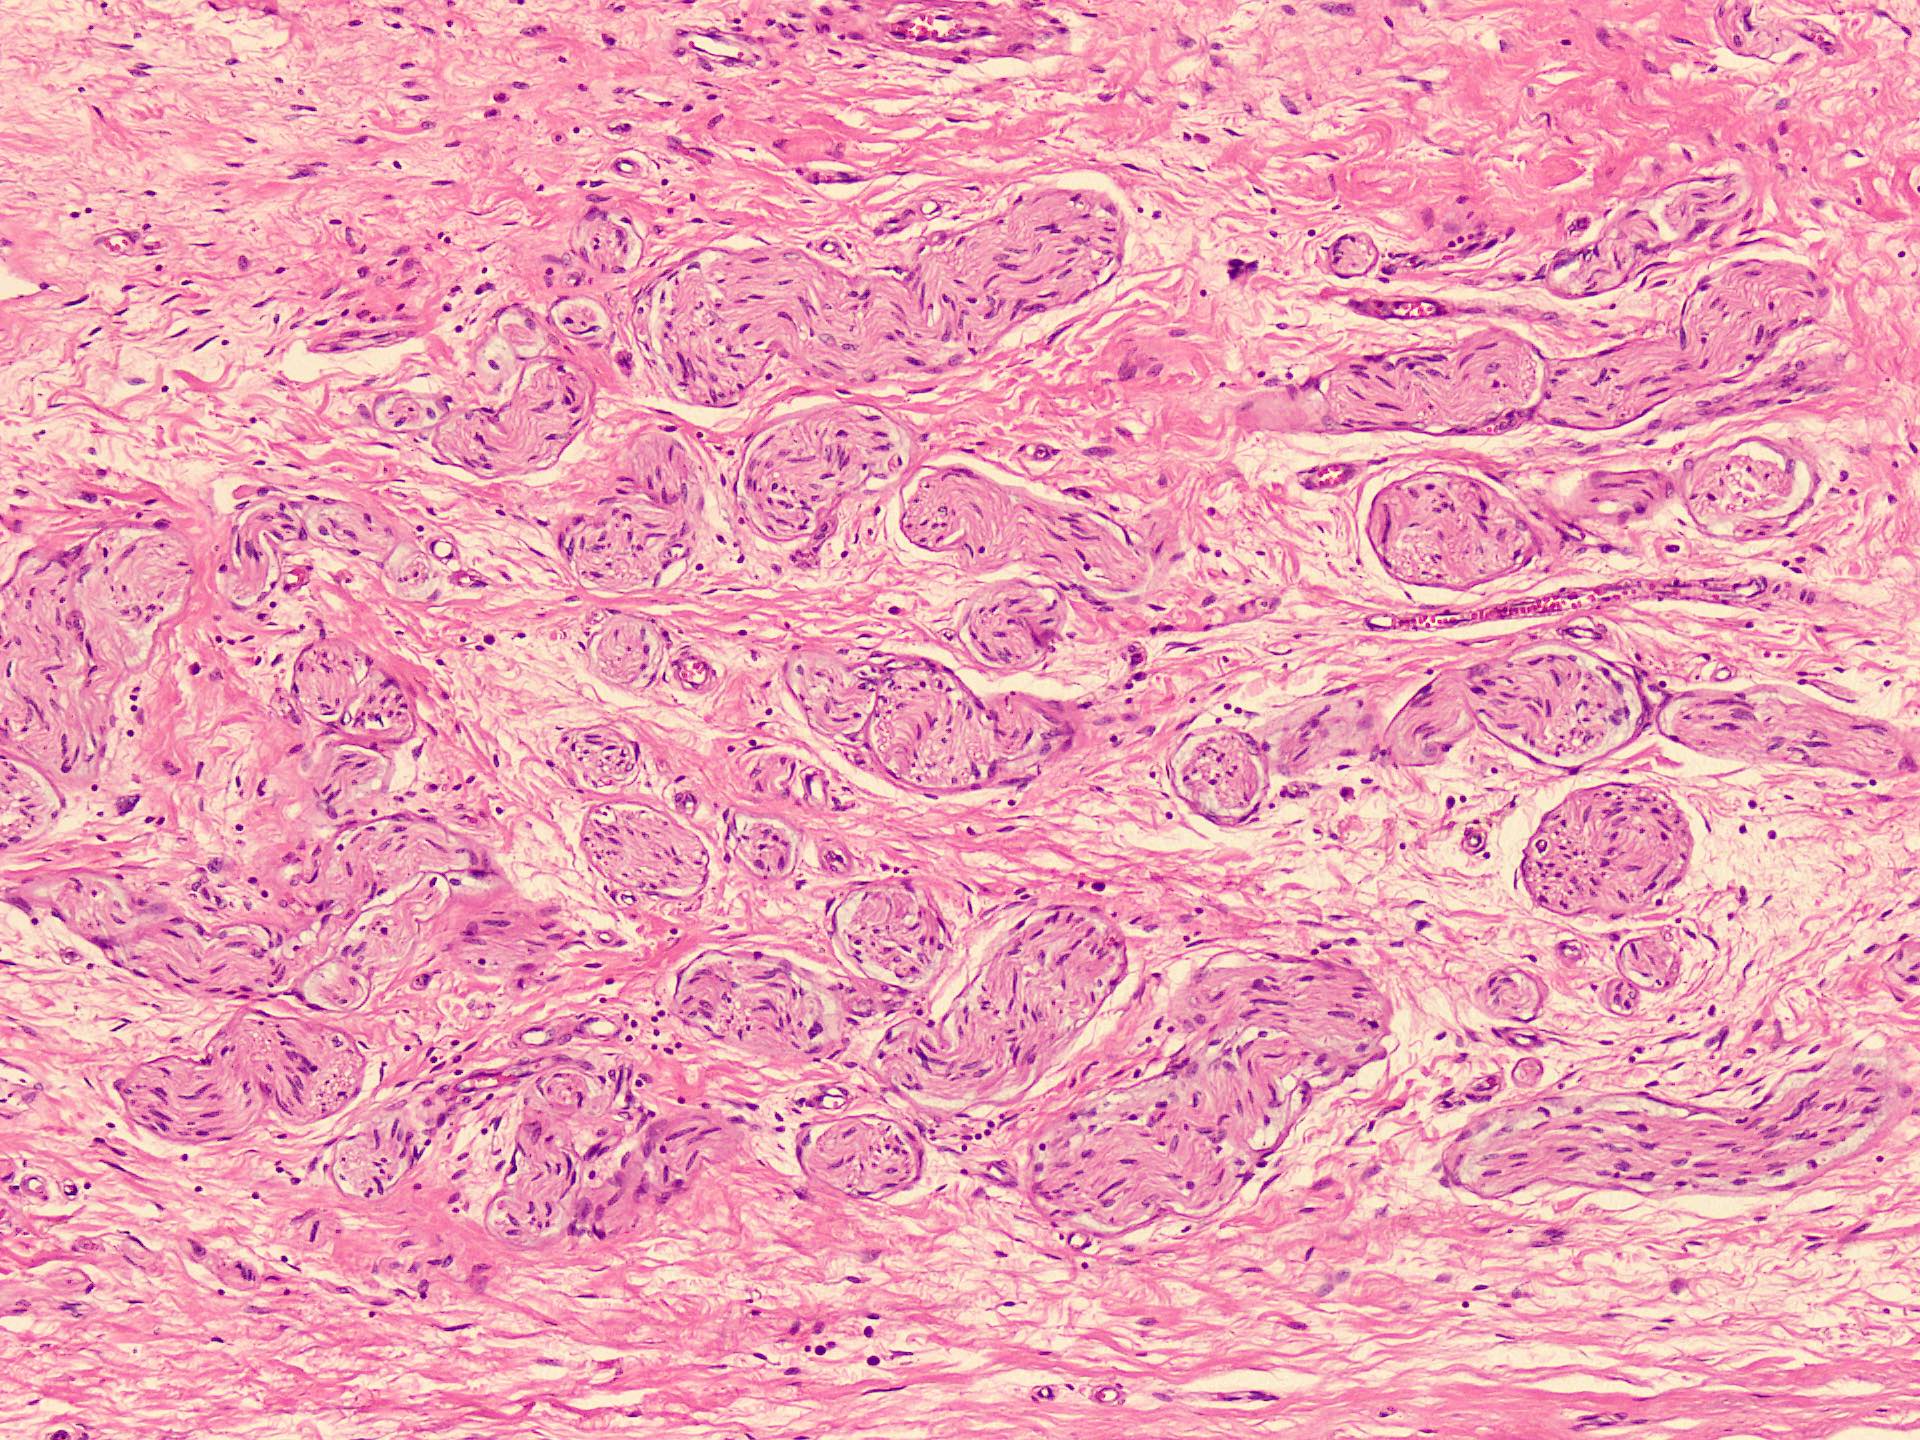

Microscopic (histologic) description

- Circumscribed, unencapsulated spindle cell proliferation arranged in short bundles comprised of axons, Schwann cells, endoneurial cells and perineurial cells (World J Clin Cases 2020;8:3821, Acta Biomed 2020;91:122, StatPearls: Neuroma [Accessed 21 September 2022])

- Peripheral palisading is not present (World J Clin Cases 2020;8:3821)

- Prominent scar tissue with dense collagen may be present (Acta Biomed 2020;91:122, StatPearls: Neuroma [Accessed 21 September 2022])

- Dystrophic calcifications are rarely present (Acta Biomed 2020;91:122)

Microscopic (histologic) images

- Microscopy: The sections examined show a circumscribed, unencapsulated lesion composed of variable sized, closely packed nerve bundle along with scar tissue in the background.

A patient presented with a painful nodule that developed after an amputation of the left first finger. On examination, the nodule is painful. Excision of the lesion is performed which shows the histology above. Which of the following is the most likely diagnosis?